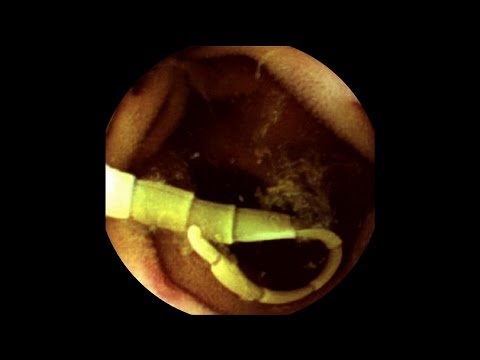

Овие морничави рентенски снимки го прикажуваат телото на еден Кинез чиешто тело насекаде е нападнато од тенија откако се прејал сашими – сирови резанки риба. Човекот отишол на лекар жалејќи се на болки во стомакот и чешање на кожата, и рентенските снимки ја откриле ужасната причина за неговите маки.

Истражувањата потврдуваат дека јадењето сирова и незготвена риба може да доведе до разни паразитски инфекции како оваа. Инфекцијата со тенија се случува откако човекот ќе внесе ларви кои се наоѓаат во слатководните риби како лососот, но и маринираните и чадените риби исто така можат да го пренесат овој црв паразит. Подобрената хигиена помага, но порастот на ваквите случаи пред сѐ се должи на зголемената популарност на сушито во целиот свет.